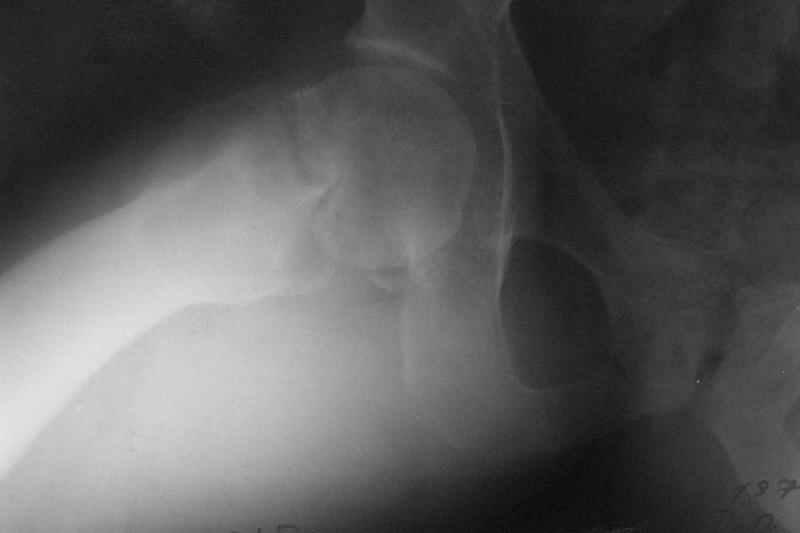

Нелеченный перелом шейки бедра / Neglected femoral neck #

Глубокоуважаемые коллеги, Вчера обратился мужчина 31 г. Травма 2 месяца назад, лечился в одном из городов области. Был не самый тяжелый перелом таза, который проведен консервативно. С ним и связывали невозможность поднять ногу.

Однако на сегодняшнем снимке обнаружился перелом шейки бедра. Больной уже ходит с частичной нагрузкой. Учитывая срок и картину на снимке, что предпринять? У нас предложены варианты 1)не оперировать, 2)закрыто 2 спонгиозных винта, 3)вальгизирующая остеотомия. Эндопротез как-то даже в список включать пока не хочется. Какие есть соображения? Что из перечисленного или что-то другое выбрать и почему? Заранее спасибо.

Dear colleagues, A male 31 years old treated elsewhere after not severe pelvic fracture, was managed non operatively. So the injury looked as a reason of his inability to elevate the leg. However at the recent x-rays the neck fractire was found. The patient already has been walking with partial weight-bearing. Looking at the x-rays and the time since the injury, what is the optimal treatment for now? We discussed 1)leave as is, 2)2 cancellows screws as is, 3)valgus osteotomy. Total hip replacement looks unnecessary yet. What is your opinion? Which option from the listed or something else should be preferred and why? THX in advance.